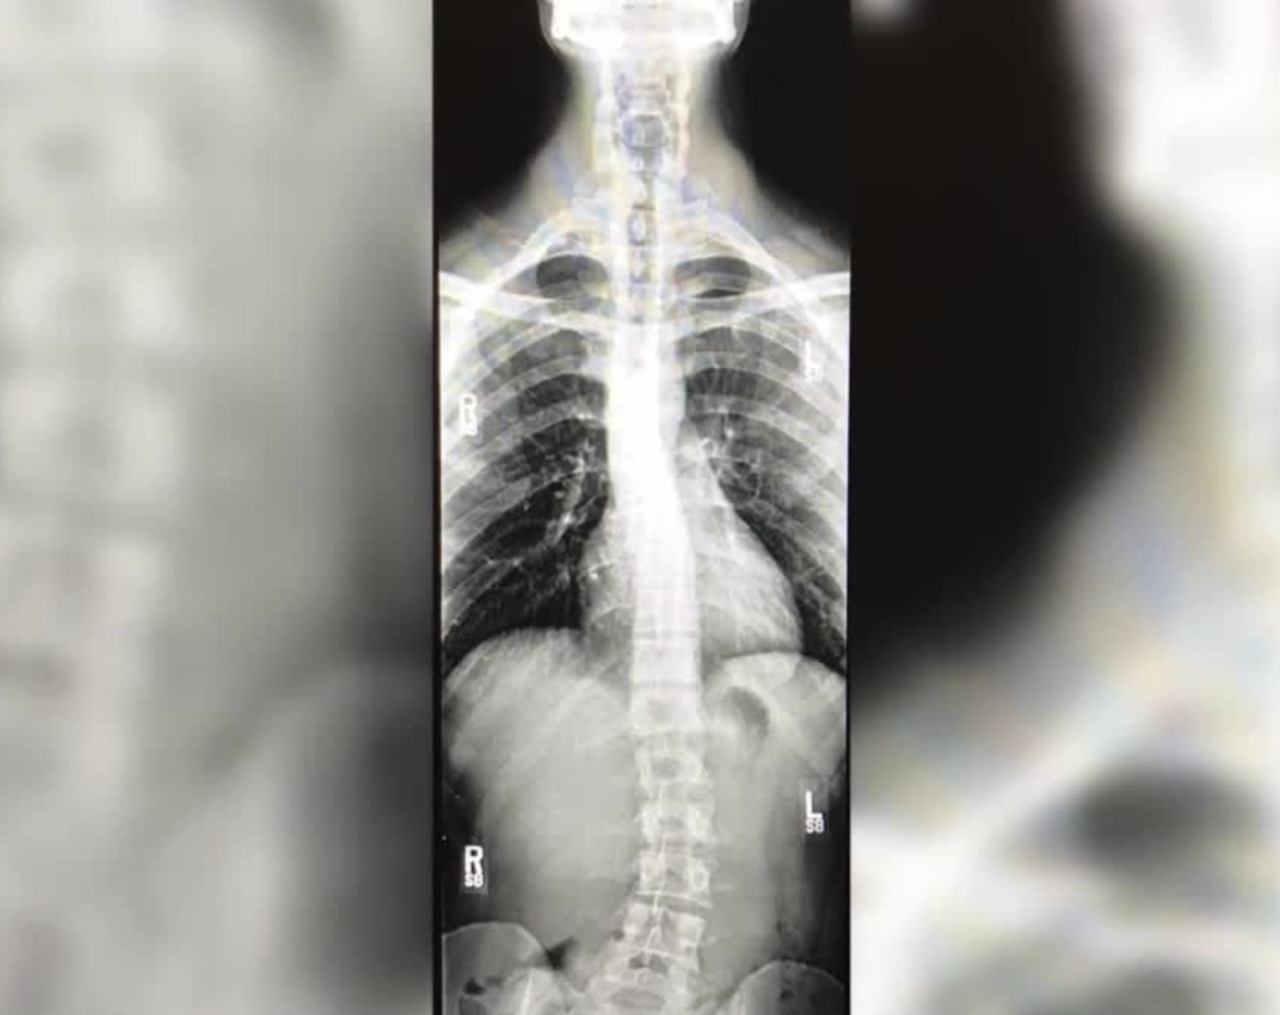

It's an extraordinary goal and when you see the X-ray of his spine, you realize this is no ordinary man.

"So not only am I dealing with some herniation and degeneration in my lower back, but I also have scoliosis. Whether that was caused by the incident, I don't know if that's exactly the case."